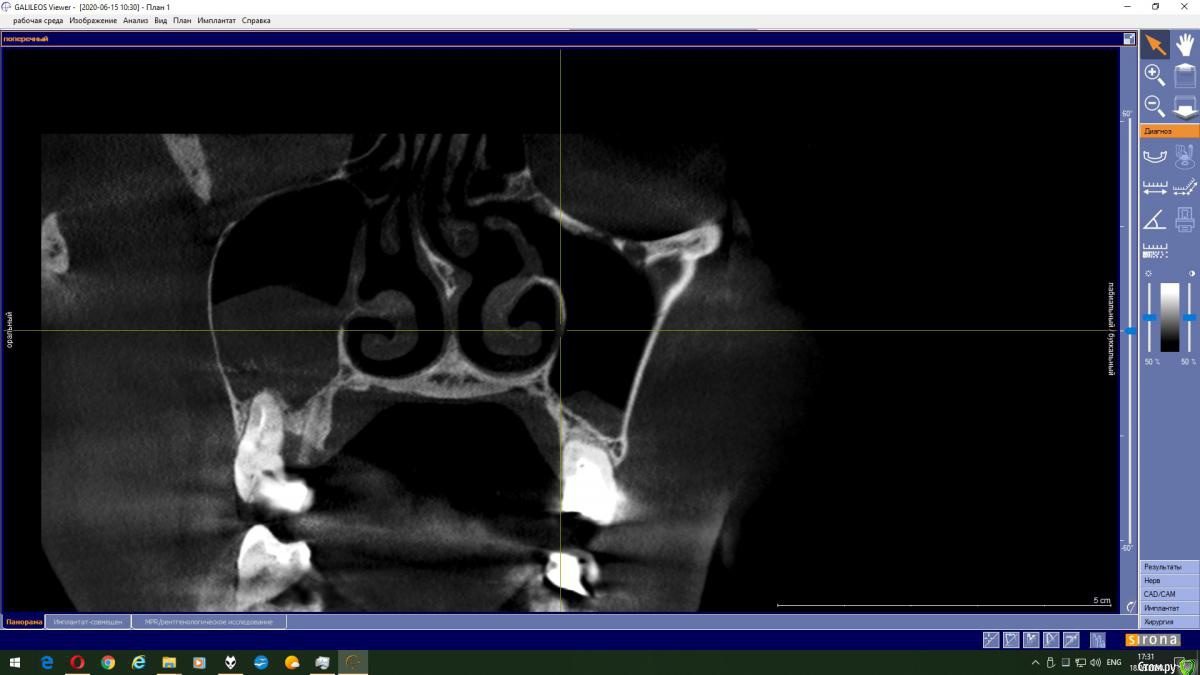

Magnoliya Опубликовано 18 июня, 2020 Поделиться Опубликовано 18 июня, 2020 Здравствуйте, прошу Вашей помощи и консультации. Все доктора, у которых я уже побывала говорят противоположные вещи, сложно принять решение. Очень надеюсь, что вы сможете посмотреть КТ, и выскажете своё мнение. http://fayloobmennik.cloud/7398744 Предыстория удалила 6 и 7 на левой верхней челюсти в надежде, что через 4 месяца сделаю открытый синус-лифтинг с подсадкой костной ткани и затем установлю импланты,но когда принесла КТ врачу перед операцией, он сказал, что синус лифтинг противопоказан, так как в гайморовой пазухе киста, и костной ткани мало, от слова ОЧЕНЬ МАЛО. В его видении решении моей проблемы был скуловой имплант Zigoma. при котором сразу после операции я выйду с зубами, естественно с другой суммой на операцию, на которую я не расчитывала. Тут я решила пойти на консультацию к другим специалистам, чтоб принять решение. На сегодняшний день есть 3 варианта, которые озвучили мне доктора: 1. Операция со скуловым имплантом с одномоментной установкой коронок2. Обратиться к ЛОРу и удалить кисту, затем синус лифтинг и т.д.3. Один врач сказал мне, что киста не мешает и можно делать синус лифтинг не удаляя кисту??? Действительно ли так? Можно ли избежать операции по удалению кисты? Заранее спасибо всем тем, кто хоть как то поможет советом Ссылка на комментарий

колесников Опубликовано 18 июня, 2020 Поделиться Опубликовано 18 июня, 2020 Глупости какие! Для чего зигомы? Доктора видимо смутил рельеф дна пазухи,там много перегородок,выступов,что затрудняет отслаивание мембраны. Можно провести имплантацию одновременно с синуслмфтингом,а кисту и вовсе не трогать. 1 Ссылка на комментарий

Irouil Опубликовано 18 июня, 2020 Поделиться Опубликовано 18 июня, 2020 Надо смотреть контур, конечно, но если позиция зигомы транссинусальная (судя по всему это так), то отношения с кистой не лучше, чем при синус лифте) Ссылка на комментарий

колесников Опубликовано 19 июня, 2020 Поделиться Опубликовано 19 июня, 2020 Выходить можно сделать синус лифтинг не трогая кисту. В дальнейшем ничем это не грозит? Я имею ввиду киста не вытечет на импланты? И может ли киста со временем рассосаться сама? это не инфекционного происхождения киста,слизистая железка закупорилась,может надуваться,может лопнуть самостоятельно,у вас она на боковой стенке пазухи,синуслмфтингу не помеха Ссылка на комментарий